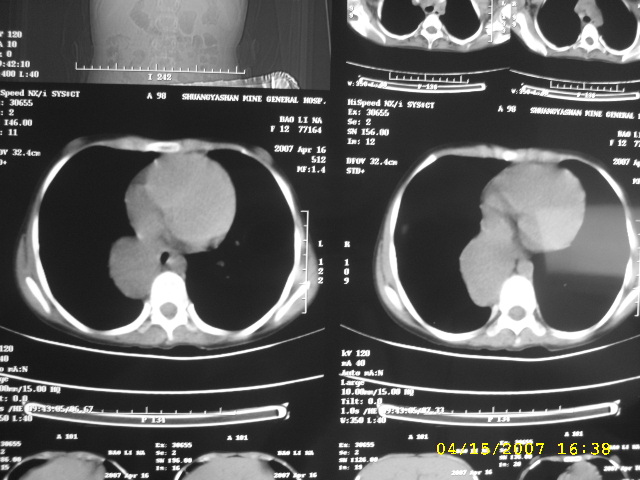

标题: PED0109:女,12,后纵隔占位十余年

女,12,后纵隔占位十余年。

女12岁,发现占位十余年,首先考虑是先天性病变:

食管囊肿

神经源性肿瘤